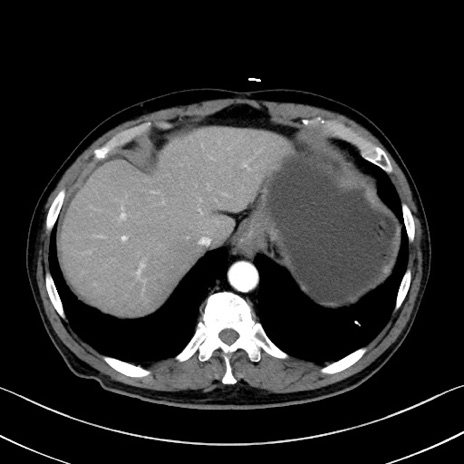

症例35(横断像)

【症例】70歳代 男性

【主訴】腹部膨満、嘔吐

【現病歴】昨日より腹部膨満感出現。本日増悪し、仙痛出現。嘔吐あり、受診。

【既往歴】糖尿病、胆摘後

【身体所見】BP 149/80mmHg、HR 74/min、BT 35.9℃、腹部:膨満、軟、圧痛なし。腸雑音減弱あり。上腹部正中切開瘢痕あり。

【データ】WBC 13500、CRP 1.72